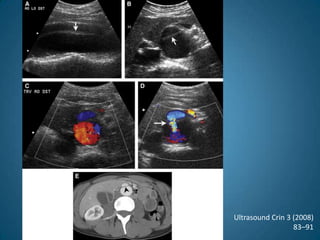

Ruptura de aneurismaUltrasound Crin 3 (2008)83–91

Ruptura de aneurismaUltrasoundCrin 3 (2008)83–91

TAC abdominalMuy sensible y específico, particularmente cuando se combinan medio de contraste, cortes finos y reconstrucciones tridimensionales con mediciones perpendiculares a la línea media de la aortaDa información precisa sobre la forma y relaciones anatómicas de los vasos renales, iliacos  y viscerales, así como la presencia de trombos murales, calcificaciones y ateroesclerosis oclusiva Se recomienda en caso de que se plantee tratamiento de reconstrucción aórticaSurg Clin N Am 91 (2011) 185–193

TAC abdominalPuede dar información errónea en el caso de aorta tortuosa, igual que la ecografíaInvasivo, pues requiere contrastes intravenosos y el uso de radiaciones ionizantesEs mas caro y de menor disponibilidad por lo que no se recomienda como técnica de screening inicialSurg Clin N Am 91 (2011) 185–193

TAC abdominalMuy sensibley específico, particularmente cuando se combinan medio de contraste, cortes finos y reconstrucciones tridimensionales con mediciones perpendiculares a la línea media de la aortaDa información precisa sobre la forma y relaciones anatómicas de los vasos renales, iliacos y viscerales, así como la presencia de trombos murales, calcificaciones y ateroesclerosis oclusiva Se recomienda en caso de que se plantee tratamiento de reconstrucción aórticaSurg Clin N Am 91 (2011) 185–193

TAC abdominalPuede darinformación errónea en el caso de aorta tortuosa, igual que la ecografíaInvasivo, pues requiere contrastes intravenosos y el uso de radiaciones ionizantesEs mas caro y de menor disponibilidad por lo que no se recomienda como técnica de screening inicialSurg Clin N Am 91 (2011) 185–193